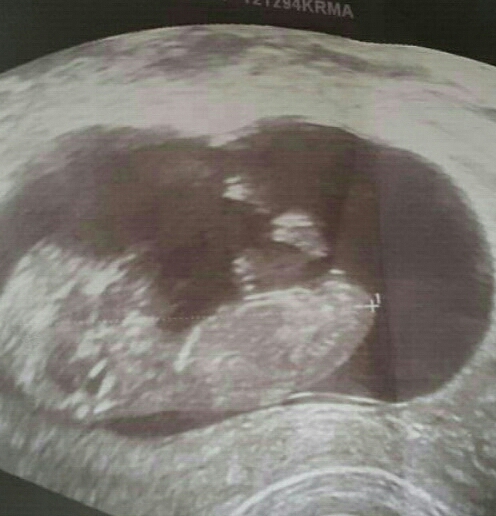

This was taken at 12 weeks scan. Pls tell me whether the nub looks like a boy or girl.